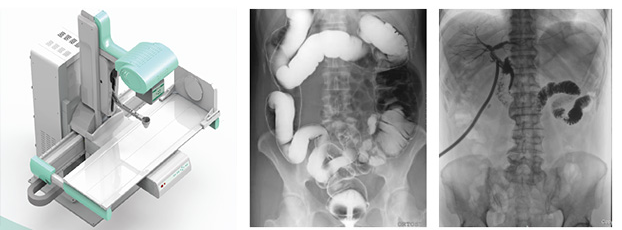

X射線檢查設(shè)備——數(shù)字DR

尤為主要的就是X射線檢查設(shè)備和CT檢查,這兩項檢查確實是具有相當大的輻射性,至少比B超和核磁共振危害大。如X射線檢查設(shè)備,是利用X射線穿透于臟腑內(nèi)并形成影像。X射線是有電離輻射的,且危害性是存在的。一次檢查,輻射量0.02~0.1之間,只要次數(shù)不多,每年只做一次檢查,那么對機體的影響是不大的。

反之,X射線檢查的次數(shù)越多,或者在檢查過程中投放了超標的劑量,有可能致癌。控制其劑量和做檢查的次數(shù),是有必要的。

CT的輻射和X射線檢查是一樣的,基本并沒有太大的區(qū)別。主要是檢查的部位,和準確性不一樣。與X射線檢查設(shè)備相比,CT是一種更為細致的檢查,它能夠檢查出身體內(nèi)更小的病灶,提升檢查結(jié)果的準確性。

相對來說,CT的輻射量,也就更大了,單次檢查在2到5個單位。當然,這種劑量依然是人體可以承受的。綜合來看,CT的輻射是比較多的,也是對人體危害比較大的。但是在控制次數(shù)的前提下,是不需要擔心的。

X射線檢查設(shè)備、CT、磁共振,三者有機地結(jié)合,能使當前影像學檢查既擴大了檢查范圍,又提高了診斷水平。看到這里,希望大家可以不用談放射色變,選擇合適的放射方式,幫助我們更好的找到病因,更快的治療疾病。如果您還想了解“新冠患者肺部的X射線影像有什么不同?看醫(yī)生怎么說”可以直接點擊該標題哦!